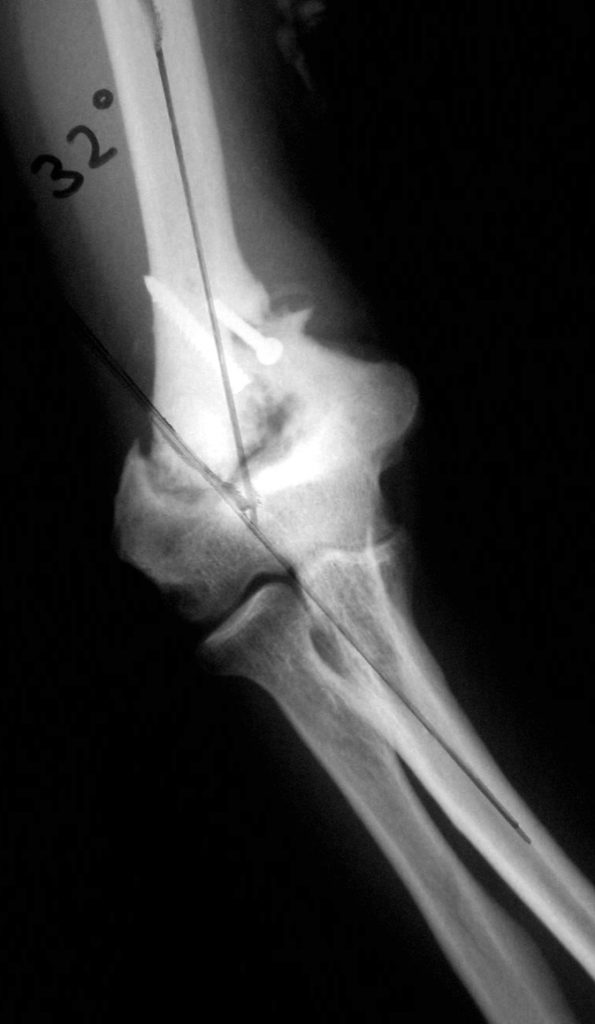

Vaka 2